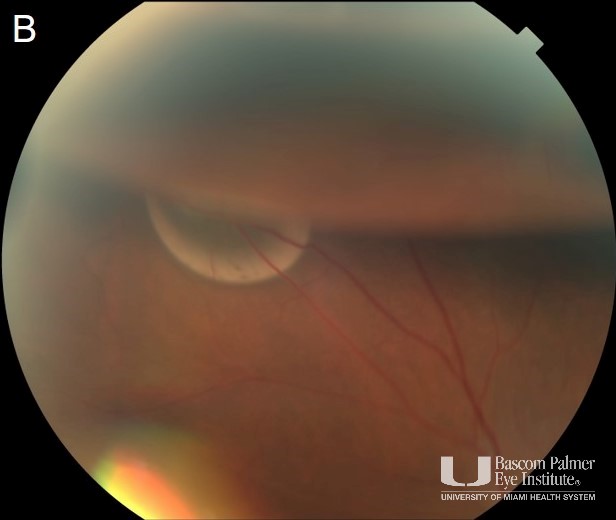

Anterior Chamber Gas Bubble After Pneumatic Retinopexy in

From bascompalmerlearn.org

Course SubRetinal Gas Post Pneumatic Retinopexy Managed with Observation What Gas Is Used In Pneumatic Retinopexy In the united states, gases used for the procedure are sf6 and c3f8. You will need to hold your head in the posturing position for 45. Rrd can occur if fluid seeps. That the gas bubble will lie against the part of the retina that needs support. These gases have the ideal properties for intraocular use in retinopexy: Sf 6. What Gas Is Used In Pneumatic Retinopexy.